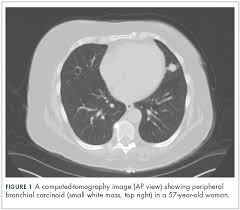

Missed Lung Lesions Side By Side Comparison Of Chest Radiography With Mdct Springerlink from media.springernature.com It can also show the size, shape, and position of any lung tumors and can help find enlarged lymph nodes that might contain cancer that has spread. This can be caused by smoking, air pollution, lung disease , or a weakened immune system. While both lung cancer and emphysema can be caused by smoking or exposure to dangerous substances, they cause different problems in the lungs and require different treatments. Copd has been linked to smoking, so simply not smoking, or quitting, will greatly reduce your risks of suffering from this condition. The flu (influenza) the common cold. Pulmonary emboli are blood clots that have formed in other regions of the body and have then traveled to the lungs. Lung cancer is an uncontrolled and uncoordinated overgrowth of the lung tissue. Shortness of breath during everyday activities.